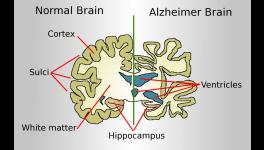

The corresponding author of the study, Willliam Seeley, a professor of neurology and pathology at the Memory and Ageing Centre and Weill Institute, has shown in his previous researches that brain atrophy in many forms of dementia is closely related to well-known brain networks. That is, group of functionally related brain regions that work cooperatively through their synaptic connections, sometimes even over long distances. In other words, these researches propose that instead of spreading evenly through the brain like that of a tumour, the neurodegenerative diseases jump from one part of the brain to another along the circuits that wire theses network together. The new study supports this idea.

The researchers began with the hypothesis that brain atrophy starts at some vulnerable region and then spreads out to anatomically connected regions via the synapses. They scanned brains of the patients to find out where the brain atrophy had begun. To do this, they built standardised maps of some 175 brain regions using FMRI (Functional Magnetic Resonance Imaging) of 75 healthy persons. They then matched these standardised maps with the scans from FTD affected people and found out the hub of the brain atrophy as the likely epicentre of the patient’s degeneration.

They used the results from this step to predict in which direction the atrophy spreads and matched their predictions with the brain scans from the FTD affected people taken a year back. They found good matches in their predictions that were based on their hypothesis. The brain atrophy spreads through the brain by synaptic connections between related brain areas. The progression starts from a vulnerable region and eventually affects other parts.